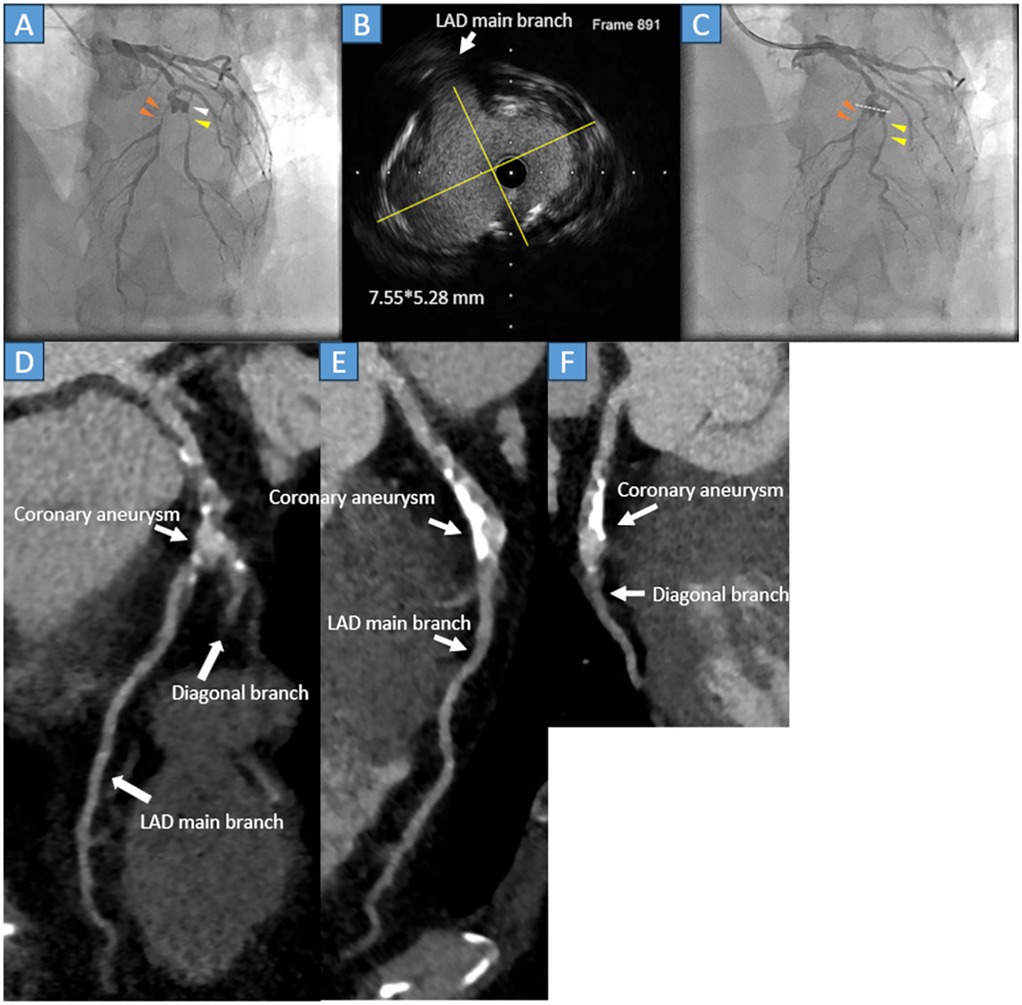

A 54-year-old male with an unknown medical history, but no prior Kawasaki disease, was admitted to our hospital because of effort angina. The treadmill stress test result was positive; therefore, an elective CAG was performed. The CAG revealed stenoses and an aneurysm in the left anterior descending artery (LAD) (Figure 2A, orange arrowheads) and diagonal branch (Figure 2A, yellow arrowheads). Subsequently, in April 2022, PCI was performed. After crossing the 0.014-inch guidewire, IVUS was performed. IVUS revealed a mildly calcified lesion and a 7.55*5.28 mm oval-shaped aneurysm (Figure 2B yellow lines, Figure 2C white dots). The LAD was treated with a 2.5*20 mm paclitaxel DCB dilating a 2.0*13 mm scoring balloon, and the diagonal branch was treated with a 2.0*15 mm paclitaxel DCB after dilating a 2.0*15 mm compliant balloon.

Medical imaging panel showing coronary artery assessments. Panel A and C feature angiographic images highlighting arteries with markers. Panel B displays an intravascular ultrasound image of the LAD main branch. Panels D, E, and F show CT scans identifying a coronary aneurysm, LAD main branch, and diagonal branch. Labels indicate specific areas of interest in each image.

Figure 2. (A) Coronary angiography reveals severe stenosis at the middle segment of the left anterior descending artery (LAD) (orange arrowheads) and the second diagonal branch (yellow arrowhead), just after the aneurysm formation (white arrowhead). (B) The cross-sectional image of the intravascular ultrasound (IVUS) detects a 7.55*5.28 mm (yellow lines) mild calcified oval-shaped coronary aneurysm. (C) The LAD (orange arrowheads) and second diagonal branch (yellow arrowheads) were successfully treated with the drug-coated balloon. The white dots in the angiography correspond to the cross-sectional IVUS image. (D) Cardiac computed tomography showing patient LAD and secondary diagonal branches with calcification. (E) The LAD is patent with atherosclerotic change and calcification. (F) The second diagonal branch is patent, and the main branch of the LAD is severely calcified.

The immediate outcome was favorable (Figure 2C, orange and yellow arrowheads) without dissection. Post-procedure, the patient was prescribed three months of aspirin, prasugrel, statins, and beta blockers; after three months, prasugrel was discontinued. During the follow-up, he did not report any chest discomfort. Approximately 3 years and 3 months later (July 2025), a repeat cardiac CT was performed. The scan revealed moderate atherosclerotic changes in the LAD. However, no stenosis was observed in either the LAD or diagonal branch (Figures 2D–F, white arrows).